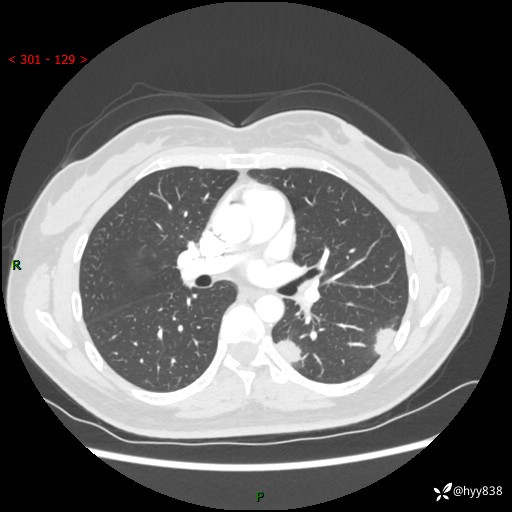

36岁/女,左侧下胸部阵发性疼痛2周,乏力1周。精彩无限,等你来诊---结果公布~

【患者信息】:36岁/女

【主诉】:左侧下胸部阵发性疼痛2周,乏力1周

【现病史及既往史】:患者自诉2周前饮酒后出现左侧下胸部阵发性疼痛,不随呼吸改变,无咳嗽咳痰、头晕头痛、咳血、呼吸困难等不适,于当地第一人民医院查胸部CT提示肺部感染,随后前往我院门诊给予抗感染(左氧氟沙星)治疗1周,自诉胸痛较前好转,感乏力、头晕,偶尔干咳,无咳痰,无发热、畏寒、胸闷、咯血、四肢酸痛、腹泻、腹痛等不适,门诊复查胸部CT提示:左肺下叶感染,病灶较前增加增大,遂以“肺部感染”收入我科。 起病以来,患者精神、饮食、睡眠可,大小便正常,体力体重无明显变化。

【检查】:胸部CT增强(外院平扫)